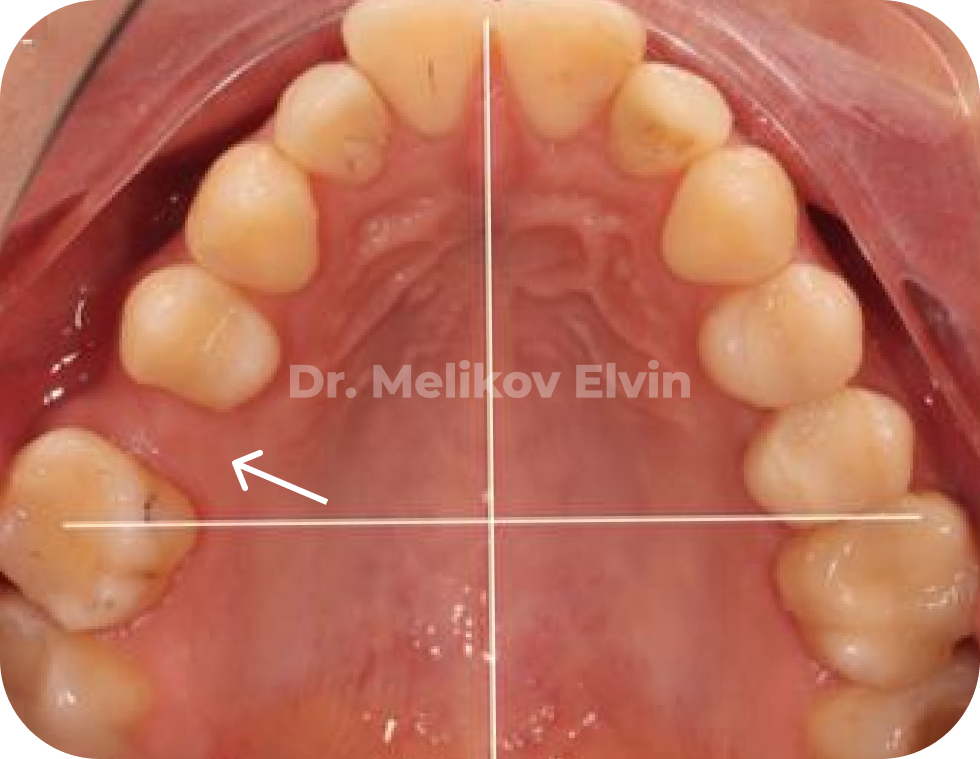

Клинический случай

🔹 Пациентка обратилась с целью стоматологической реабилитации с использованием дентальных имплантатов.

🔹 Жалобы на отсутствие зуба 1.5 и 3.6, которые были потеряны вследствие осложнения кариеса.

❗️Выявлена аномалия прикуса.

Рекомендованное лечение:

1) Коррекция прикуса с помощью ортодонтического лечения и ортогнатической операции.

2) Дентальная имплантация и протезирование.